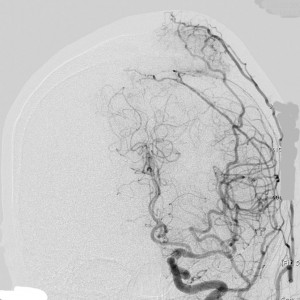

上矢状洞髄膜腫 superior sagittal sinus meningioma

上矢状洞を埋め尽くすように増大して,頭蓋骨浸潤が著しい髄膜腫ですが,ごく軽度の右足脱力以外に何の症状もありません。上矢状洞はゆっくり閉塞すれば,このような頭頂部から後頭部にわたる広範閉塞でも,静脈還流に障害がない場合が多いといえます。大脳の前半部の血流は前頭葉表面の皮質静脈から海綿静脈洞に側副路を形成しています。頭蓋内圧亢進所見もなく,これらはこの髄膜腫がゆっくり増大したということを示唆しています。

手術直後の画像です。全部いっぺんに摘出するのは無理なので,まず前から80%くらいの腫瘍を摘出しました。肥厚した骨はチタンプレートで置き換えてあります。後頭部の上矢状洞内と大脳鎌に少し残りましたが,この6ヶ月後に2回目の開頭術をして全摘出しました。結果的にこの例では,上矢状洞を冠状縫合のあたりから,静脈洞交会まで壁ごと全部摘出しましたが,脳浮腫も何も生じませんでした。腫瘍の両側にある皮質静脈 cortical veinsを損傷しないことが肝要です。